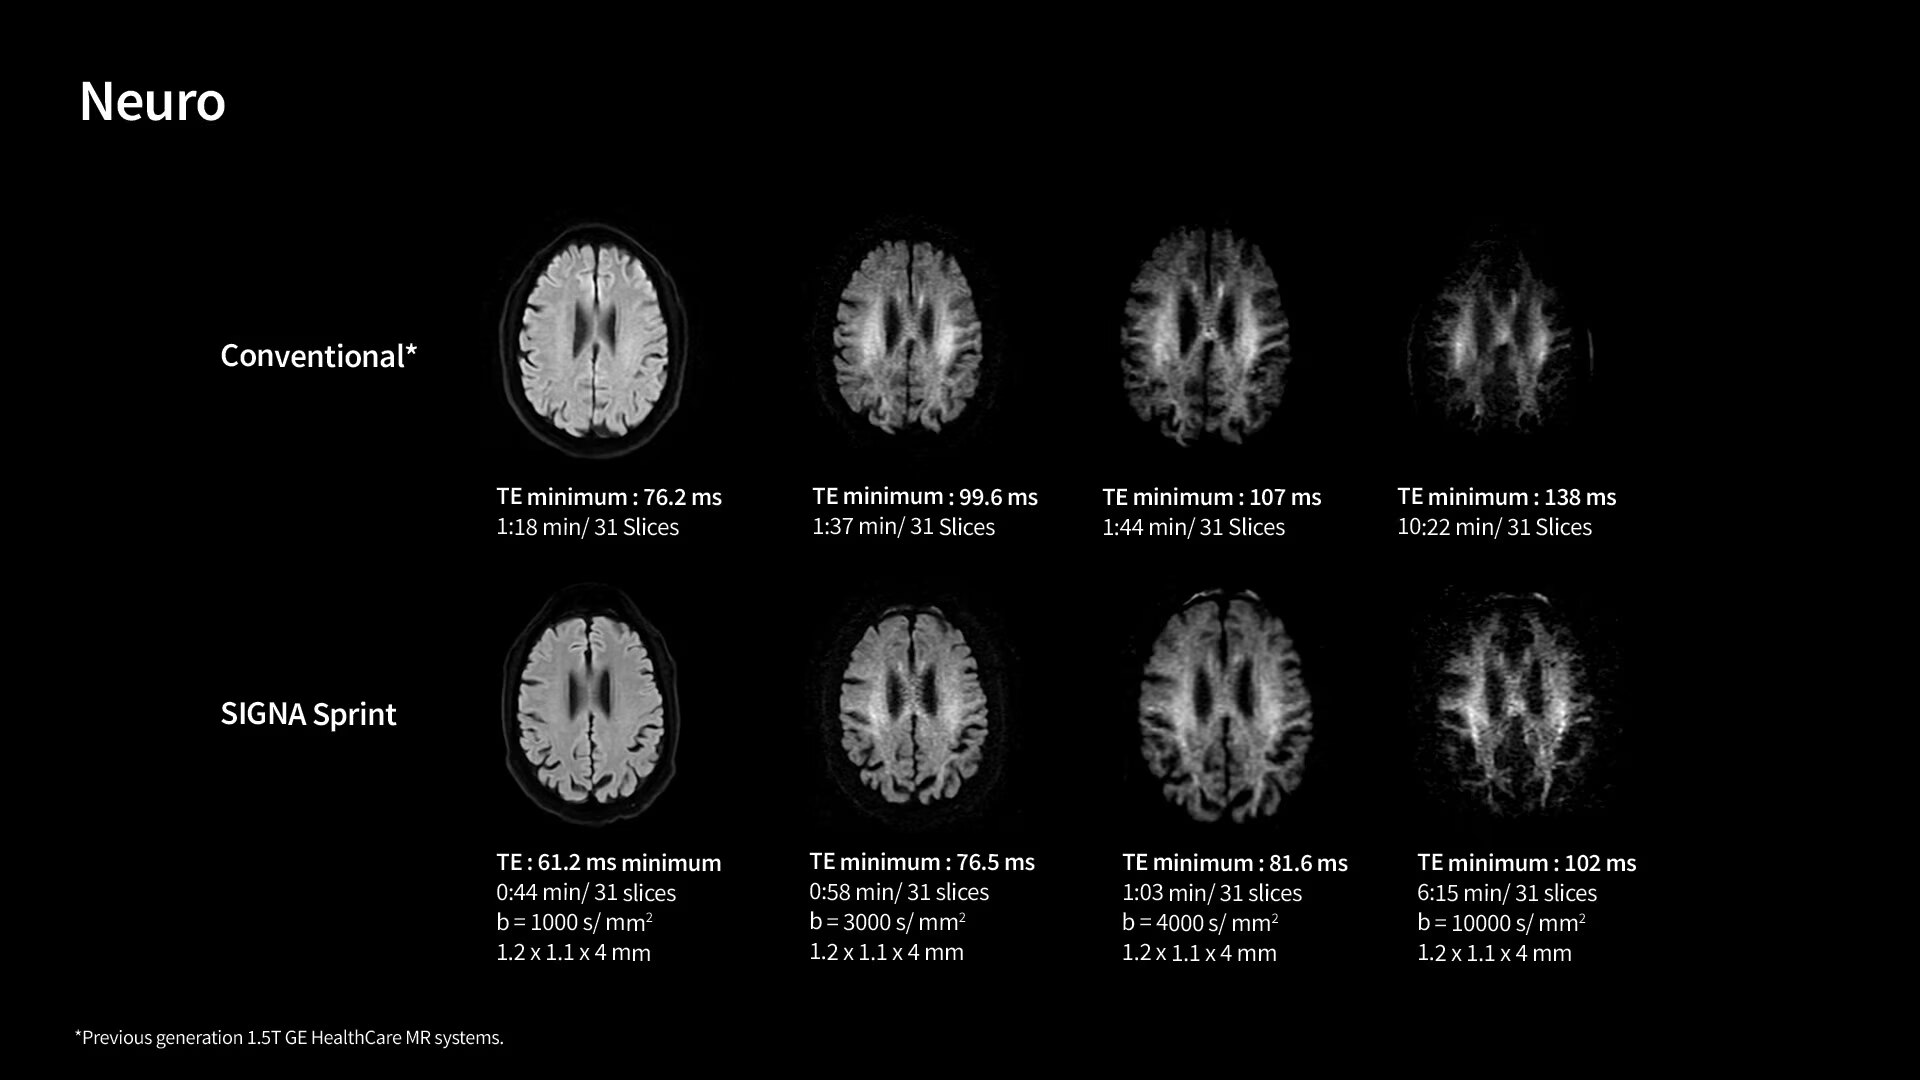

In oncological assessments, diffusion imaging is a critical clinical indicator. SIGNA Sprint offers clearer diffusion, reduced distortion and improved SNR.¹

1. Compared to other GE HealthCare legacy systems.